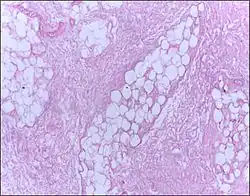

Micrograph of breast tissue showing fat necrosis. H&E stain

Fat necrosis is necrosis affecting fat tissue (adipose tissue).[1] The term is well-established in medical terminology despite not denoting a specific pattern of necrosis.[2] Fat necrosis may result from various injuries to adipose tissue, including: physical trauma, enzymatic digestion of adipocytes by lipases,[3] radiation therapy,[4] hypoxia, or inflammation of subcutaneous fat (panniculitis).

The gross appearance of fat necrosis is as an irregular, chalky white area within otherwise normal adipose tissue.[1]